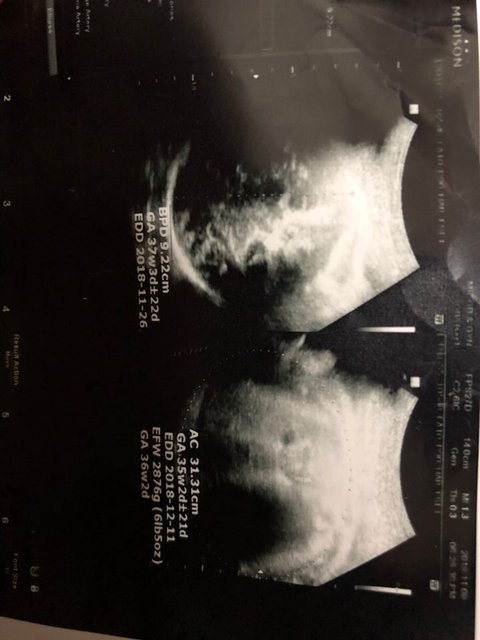

친구가̌̈ 임신했다는데

연락 안하다가 갑자기 와서는 친구가̌̈ 임신했다고 38주라는데 맞는지 안맞는지 설명좀 ,,